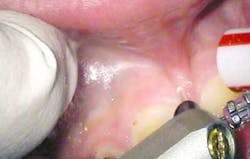

The following is a case report of one such procedure using the Opus Duo, a dual Er:YAG and CO2 dental laser system. This case begins with the diagnosis of a frenal attachment connected to the interdental papilla between maxillary central incisors (No. 8 and No. 9). The muscle attachment is bulky, and would inhibit further orthodontic correction. This patient was referred by her orthodontist for a minimally invasive laser frenectomy procedure before the next stage in her orthodontic treatment (figure 1).

After infiltration of 1cc of local anesthetic solution, the Er:YAG laser (OpusDuo, OpusDent USA) was used at 350mj with a 1,000-micron, contact sapphire tip and heavy water spray to gently ablate the frenal attachment and underlying muscle tissue down to the level of the periosteum (figures 2, 3, and 4). Once this is accomplished, there is a small defect in the vestibular mucosa and interdental papilla where the frenal attachment and muscle once was. There is no charring, no burned tissue, and free bleeding in the site (figure 5).